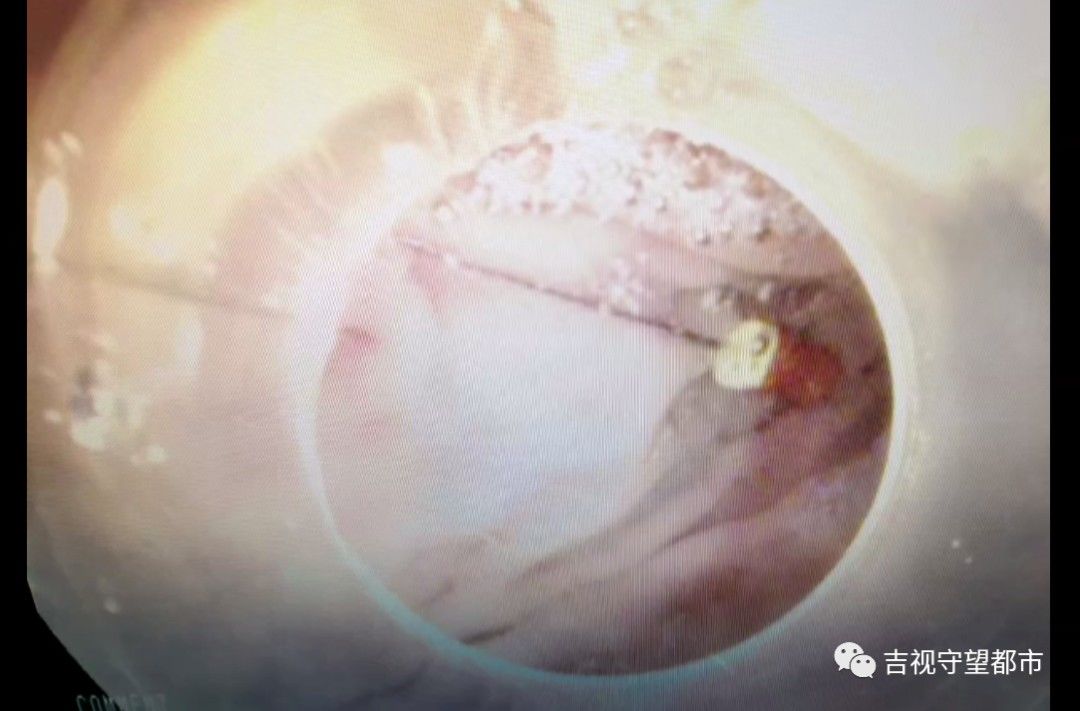

这个取出过程中,我们就需要保护这种消化道黏膜,因为那个针特别尖锐,取出的过程中,如果要是再刺伤这个消化道黏膜,可能会造成二次损伤,所以我们当时就在内镜前端装了一个透明帽,然后用这个透明帽把这个针放到这个透明帽里,这样就把黏膜保护起来,所以取完之后,孩子的消化道黏膜没有任何损伤。

仅3分钟,医护团队就将这根4厘米长的修牙针成功取出,使患儿转危为安,目前已经出院。